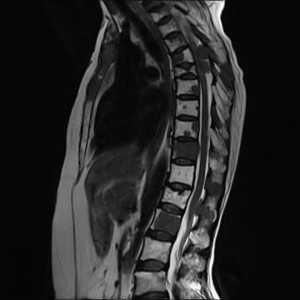

Стандартный протокол МРТ исследования позвоночника при подозрении на метастатическое поражение состоит из Т1-зависимых сагиттальных МРТ позвоночника и Т2-зависимых МРТ с подавлением сигнала от жира. Литические метастазы замещая костный мозг выглядят гипоинтенсивными на Т1-зависимых МРТ. На Т2-зависимых МРТ позвоночника они могут быть гипоинтенсивными, изоинтенсивными, если они склеротические, либо яркими, если они литические, особенно при подавлении сигнала от жира. Метастаз может диффузно поражать костный мозг позвонка или быть очаговым. На самой ранней стадии диффузного поражения заметно исчезновение сигнала при МРТ позвоночника от вертебробазилярной вены, процесс захватывает ножки дуг и задние структуры позвонка. Параспинальное распространение лучше видно на Т1-зависимых коронарных МРТ срезах, а компрессия спинного мозга на сагиттальных МРТ. На последнем этапе желательны контрастированные Т1-зависимые МРТ позвоночника в сагиттальной и поперечной плоскостях. Чувствительность МРТ превышает 90%, что заметно превосходит радионуклидную диагностику. В плане дифференциации метастазов и доброкачественных заболеваний МРТ не абсолютно надежна. Дифференциальная диагностика с гематологической патологией – плазмоцитомой, лимфомой и лейкозами практически невозможна и требует аспирационной биопсии. Реакцией костного мозга, напоминающей метастатическое поражение, сопровождаются доброкачественные переломы. Однако сигнал при МРТ позвоночника выражено неоднородный, задние структуры и костный мозг в заднем отделе тела позвонка остаются интактными. Более надёжным в плане дифференциальной диагностики является использование диффузионно-взвешенных МРТ. При доброкачественном переломе через 1 – 3 месяца сигнал возвращается к норме.

МРТ позвоночника. Сагиттальная Т1-зависимая МРТ. Множественные метастазы в позвоночник.

МРТ позвоночника. Сагиттальная Т2-зависимая МРТ. Множественные метастазы в позвоночник.